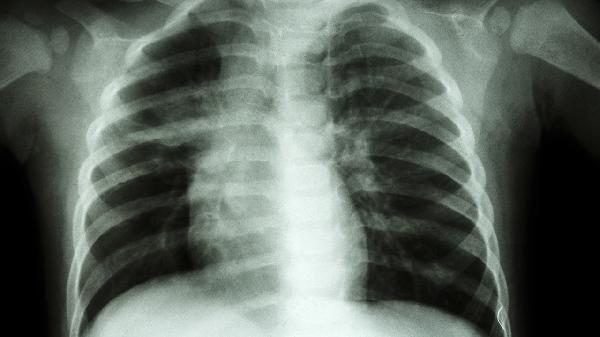

肺部感染或结核累及胸膜时,会出现呼吸相关性胸痛,伴随咳嗽、低热等症状。需进行胸部CT和胸腔积液检查,治疗可使用盐酸左氧氟沙星片、异烟肼片或醋酸泼尼松片。卧床休息时建议患侧卧位,保持室内空气流通。